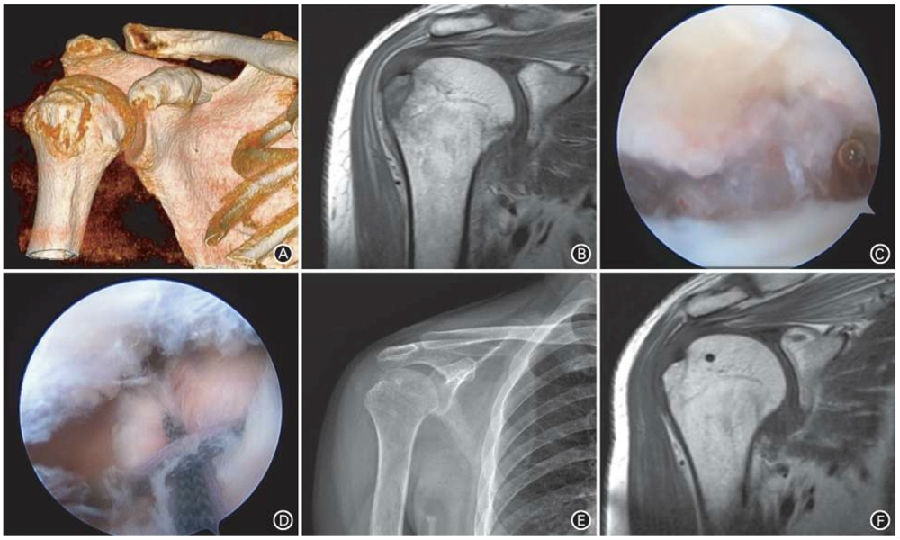

患者男,35岁,右上肢摔伤后疼痛2周,诊断为肱骨大结节撕脱骨折,采用肩关节镜下平衡点压配交叉缝线桥技术治疗。

图2 典型病例。

A术前CT三维重建示右肱骨大结节撕脱骨折;B术前MRI T1像示肱骨大结节骨折;C术中见大结节骨折面;D术中关节镜下平衡点压配交叉缝线桥技术治疗大结节骨折;E术后6个月正位X线片示骨折已愈合,骨折线消失;F术后6个月MRI T1像示骨折愈合